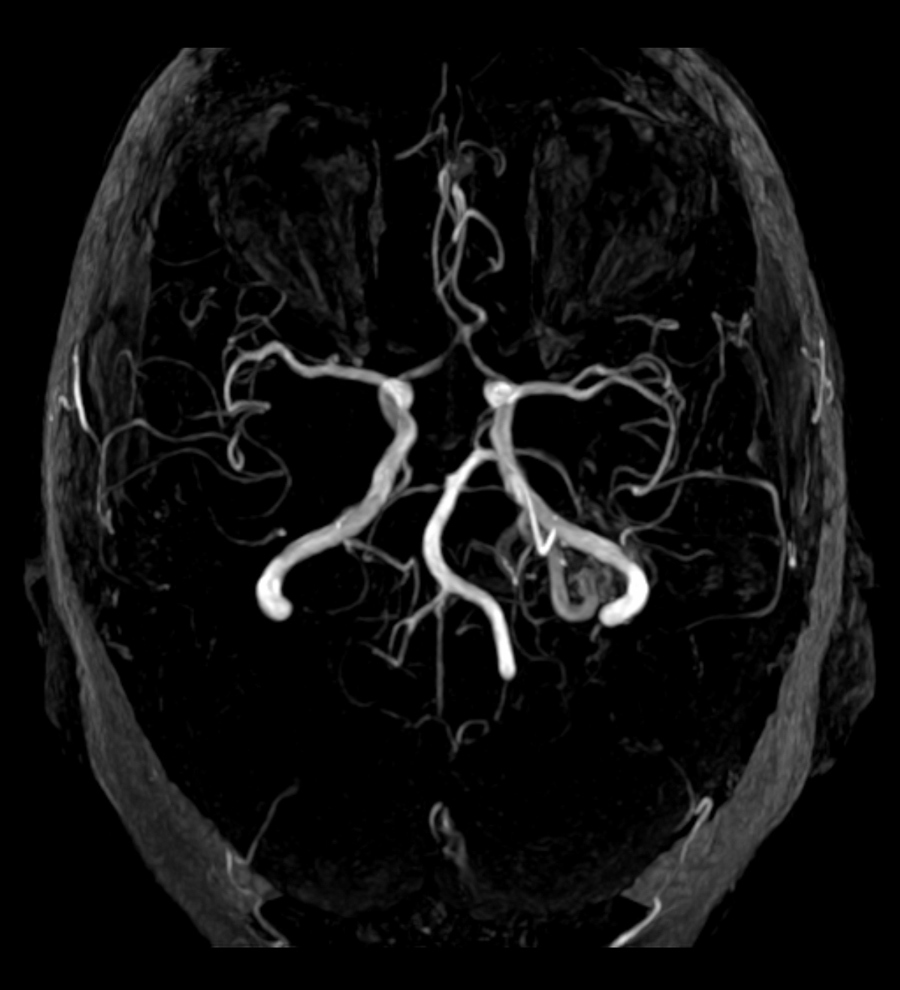

HHT极低诊断条件,如果没有管理,可能导致严重发病和死亡当前HHT结合诊断出临床标准Curaçao标准与遗传测试或未显示已知HHT基因中的致病变异约50%的病人开发肺动脉片片片,80%开发肝动脉片片片,10%开发脑动脉片片片,1%开发脊动脉片片片片,所有这一切都可能导致危及生命出血和其他并发症HHT筛选病人至关紧要,但当前诊断屏费用昂贵,无法使用,使病人接触不健康的辐射量这使得需要识别更多生物标志

后期Tabruyn等研究并支持检测循环MIRs帮助筛选HHT病人的想法检测发现MiR-27a等离子体水平显著提高,而HHT1和HHT2病人miR-205水平与健康控制值相比显著下降有趣的是,他们展示MiR-205表达式调制TGF路径,为MiR-205调制表达式和HHT提供功能链路iR-205可能不仅是HHT标志,也可能是潜在的治疗目标最近RuizLlorente等2020年显示循环MiRs可区分HHT1或HHT2病人,这可大大改善诊断过程研究MiR-370预测目标英格特HHT1下调,但不是HHT2病人,而MiR-10a预测目标ACVRL1HHT2上调,但不是HHT1病人通过进一步研究,循环MIRs可提供快速、廉价、安全相对非渗透性筛选测试诊断AVCs和HHT